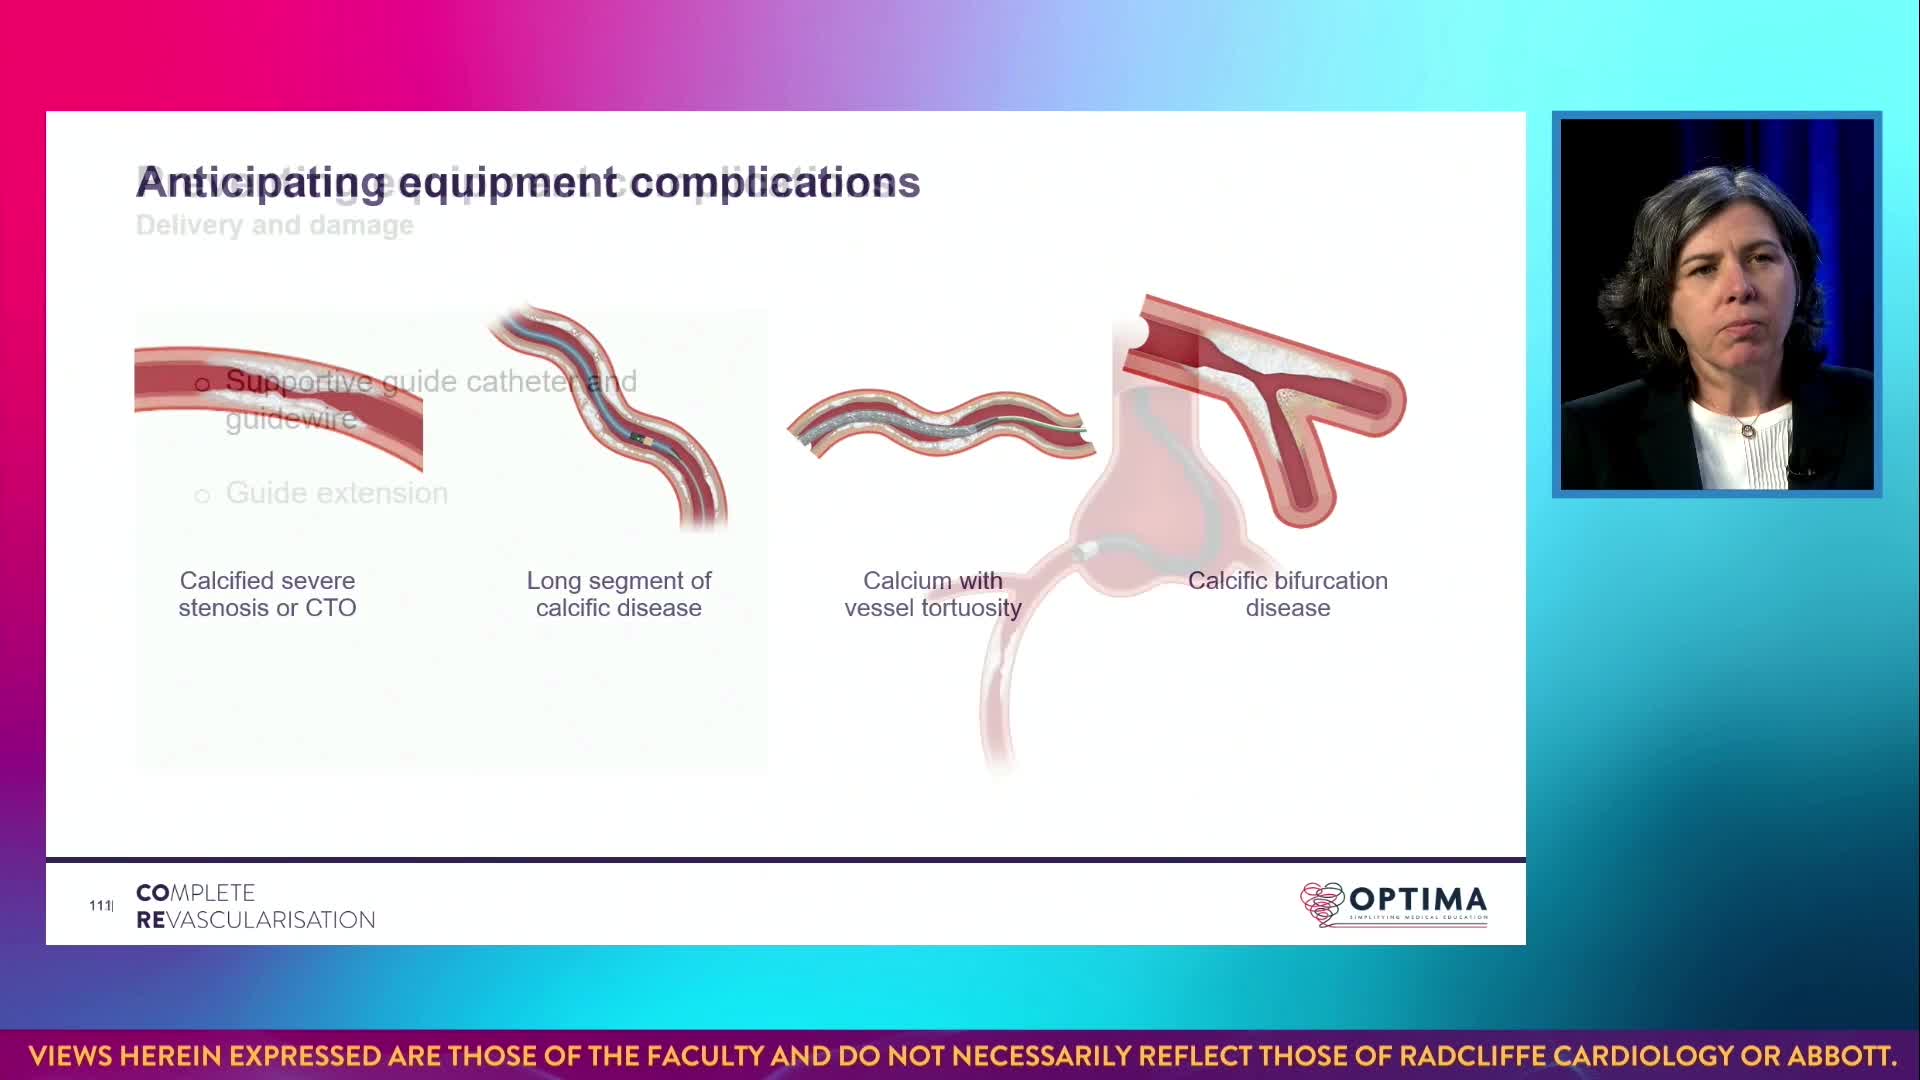

Gulf-Optimal Chronic Total Occlusion: Bahrain Event - Day 1

Gulf-Optimal Chronic Total Occlusion: Bahrain Event - Day 2

Gulf-Optimal Chronic Total Occlusion: Live Case Follow Up